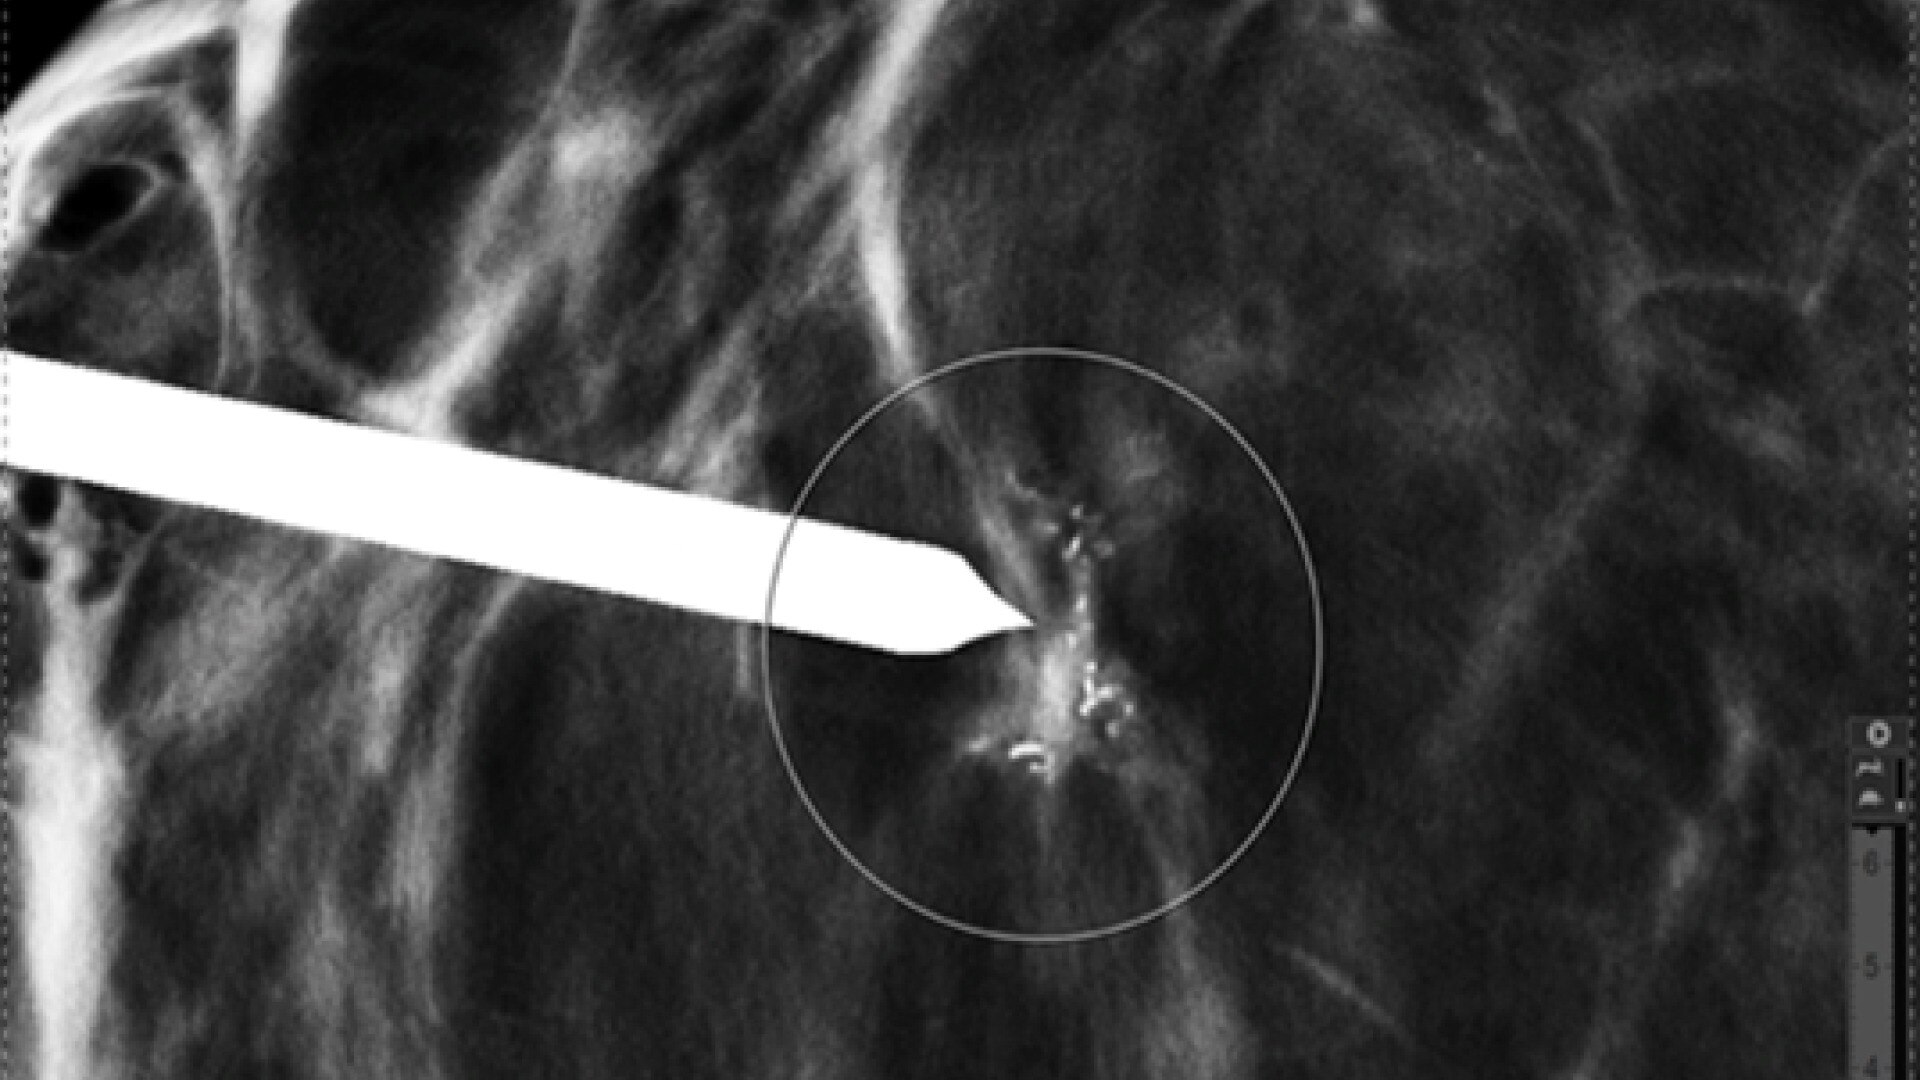

El movimiento inesperado del paciente supone siempre un reto en la IRM, lo que da lugar a artefactos fantasma que pueden dificultar el diagnóstico. PROPELLER es una técnica de adquisición radial similar a FSE que es insensible al movimiento, capaz de realizar los mismos contrastes y ponderaciones que FSE 2D y DWI. Con el lanzamiento de la versión RM 30, AIR™ Recon DL es ahora compatible con PROPELLER, lo que facilita el diagnóstico de las anatomías difíciles a partir del movimiento y la distorsión.

Productividad en un abrir y cerrar de ojos

Observe cómo aumenta la productividad con exploraciones lo suficientemente rápidas como para adaptarse al ritmo de los flujos de trabajo de sus departamentos. Sonic DL™ reduce el tiempo de exploración hasta un 83 %** al tiempo que mantiene el valor de diagnóstico. En el área crítica de la adquisición de imágenes cardiacas, una aceleración hasta 12 veces mayor significa capturar anatomías en movimiento rápido, como las válvulas cardiacas, de forma fácil y precisa. Ahora puede alcanzar la cima entre la rapidez y la calidad de diagnóstico con la aceleración Sonic DL™.